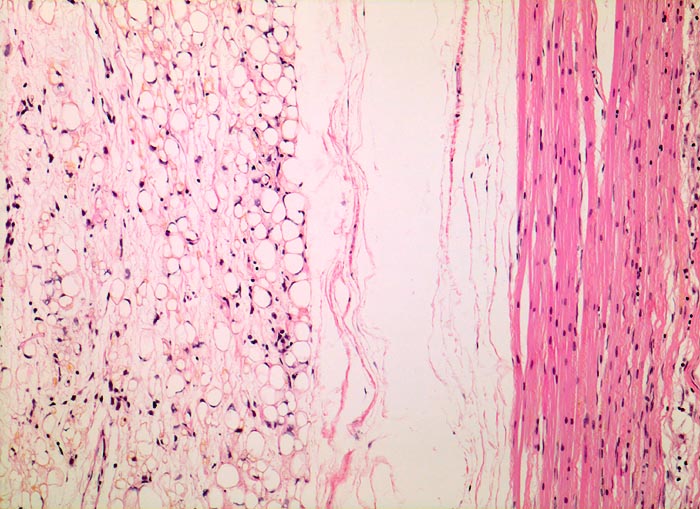

• Am rechten Rand des Präparates komprimierte Skelettmuskulatur.

• Links daran angrenzender scharf begrenzter Tumor mit reichlich myxoidem Stroma.

• Zahlreiche, überwiegend univakuoläre Lipoblasten. Zellkern durch die Lipidvakuole komprimiert und zur Seite verdrängt.

• Zahlreiche krähenfussartig verzweigte Kapillaren.

• Die rundzelligen Anteile erscheinen in der Übersicht aufgrund des Zellreichtums dunkler. Sie bestehen aus dicht gelagerten zytoplasmaarmen Tumorzellen mit vesikulären runden Kernen und einem prominenten Nukleolus.